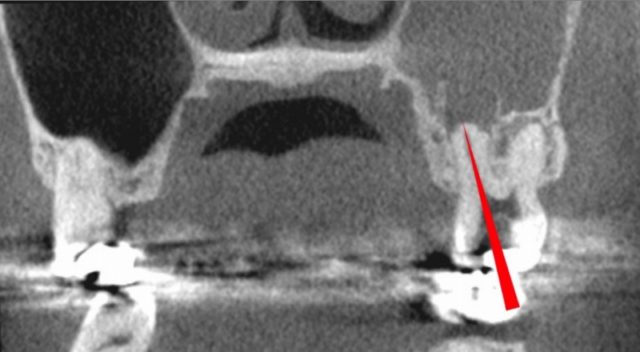

頬骨 痛いとき 急性上顎洞炎の治療

慢性上顎洞炎が、突然、急性化し、

顔が痛いし、頬骨も痛いほどの

急性上顎洞炎がおきました。

緑矢印 正常な上顎洞

黄矢印 膿がたまっている上顎洞

赤矢印 原因になった歯根

(上顎洞の底の骨が、溶けています)

頬骨 痛いとき 急性上顎洞炎の治療 根管治療 CTで根管長測定1

根管治療の前に、CTで根管長測定します。

18.6mm。

横から見た歯です。

頬骨 痛いとき 急性上顎洞炎の治療 根管治療 CTで根管長測定2

後から見た歯です。

根管長は、18.9mです。